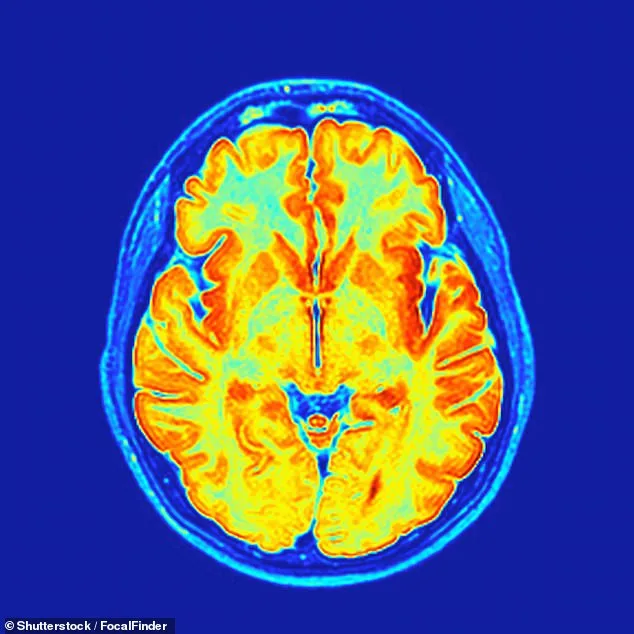

The study found that expectant mothers experience a measurable loss of grey matter—a critical component responsible for processing emotions, information, and empathy—amounting to nearly five per cent on average. This decline, however, is not a sign of deterioration but rather a form of neural pruning. Lead researcher Professor Susana Carmona of the Gregorio Marañón Health Research Institute explained the process as akin to trimming a tree, where certain branches are removed to enhance efficiency and focus. 'This rewiring is not about losing capacity but about adapting to the demands of motherhood,' she stated. The brain, she added, is undergoing a strategic overhaul to better support the emotional and cognitive challenges of raising a child.

While grey matter volume partially recovers within six months postpartum, the initial changes suggest a deliberate preparation for maternal instincts. This shift may help explain why new mothers often report heightened emotional sensitivity and an increased ability to interpret their infants' needs. The study's findings also highlight the role of hormonal fluctuations and vascular changes in driving these neural transformations, underscoring the intricate interplay between biology and environment during pregnancy.